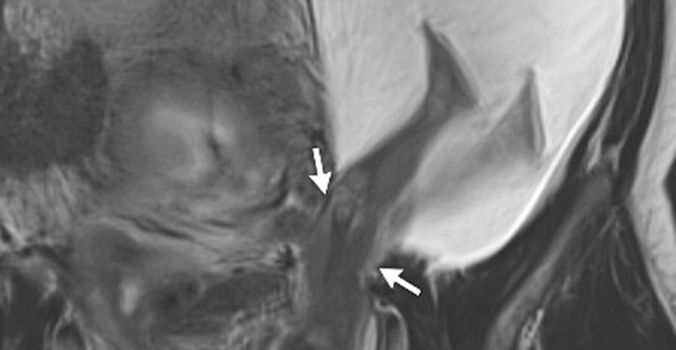

According to the report, published in The New England Journal of Medicine, magnetic resonance imaging revealed a 2.5-cm rupture of the left uterine wall (highlighted in the following image by the white arrows).

A herniated sac had grown outside the uterus and contained the baby’s abdomen and legs.